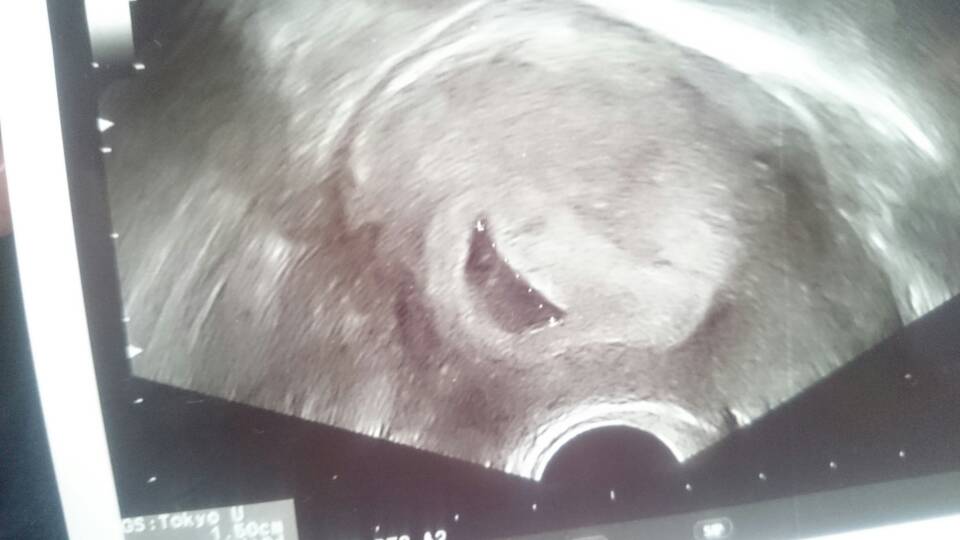

usg 4d spokojnie 13 tydz